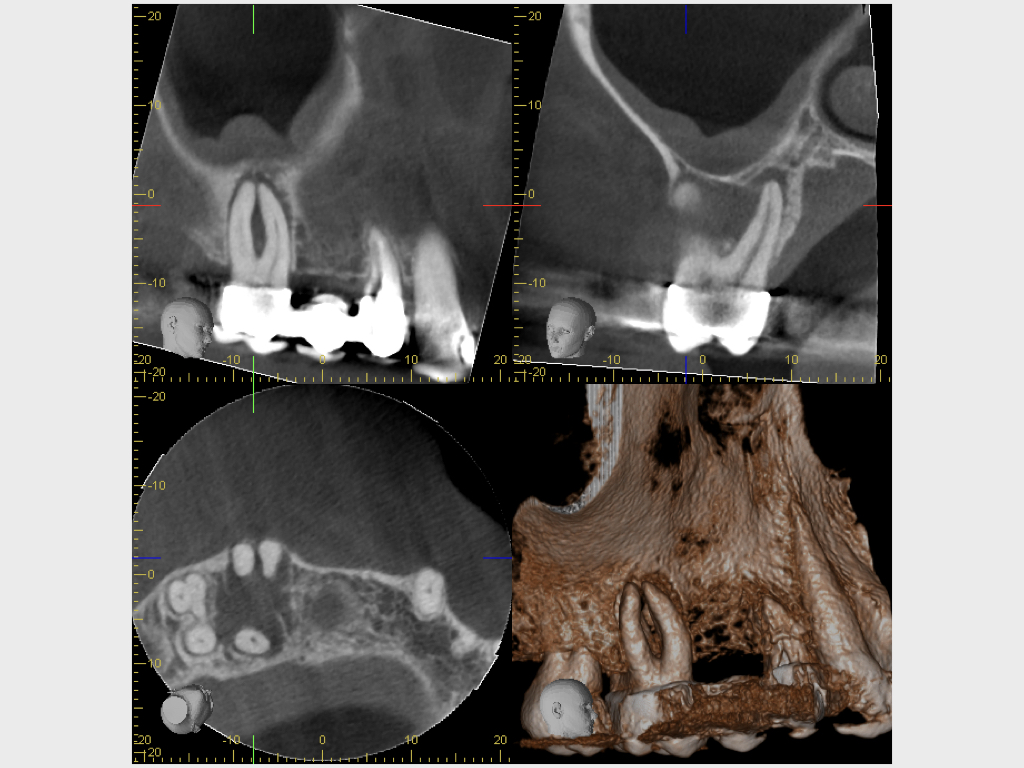

Heilung Express oder Radiodontics